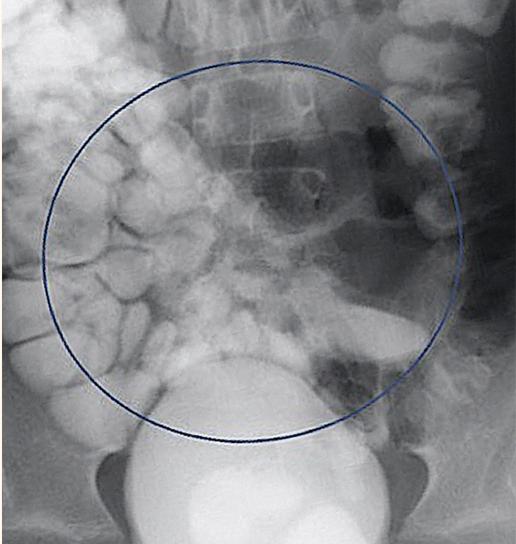

腹部和骨盆的CT与静脉造影显示多个突出的空气和充满液体的肠袢贯穿腹部。结果涉及回肠-回肠、回肠-结肠和结肠-结肠肠套叠累及远端横结肠/近端降结肠(图3、4、3、4)。在影像学证实的情况下,通过荧光剂对比灌肠对回肠-结肠肠套叠进行复位。插入一根儿童直肠管,通过重力将约360cc稀释的泛影葡胺直接注入结肠。本研究发现造影剂在整个结肠内自由流动,容易回流到回肠末端,表明在此手术之前成功减少或自发消退了轻微的回肠-结肠肠套叠 (图5)。

图5、最终图像显示造影剂回流至小肠袢(蓝圈)